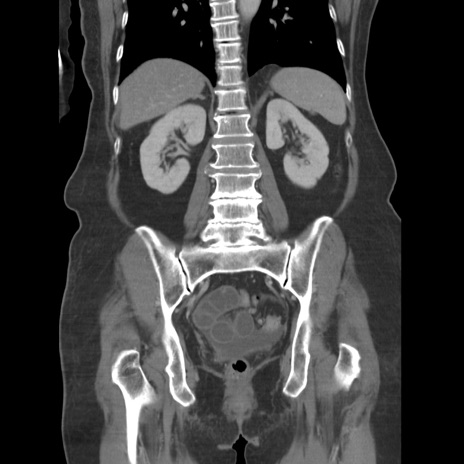

症例19(冠状断像)

【症例】80歳代女性

【主訴】下腹部痛

【現病歴】約8時間前より下腹部痛の出現あり、救急外来受診。

【既往歴】両側付属器切除

【身体所見】意識清明、下腹部正中に手術痕あり、その部位に一致して圧痛と反跳痛あり。腸蠕動音は亢進。

【データ】WBC 9300、CRP 0.15